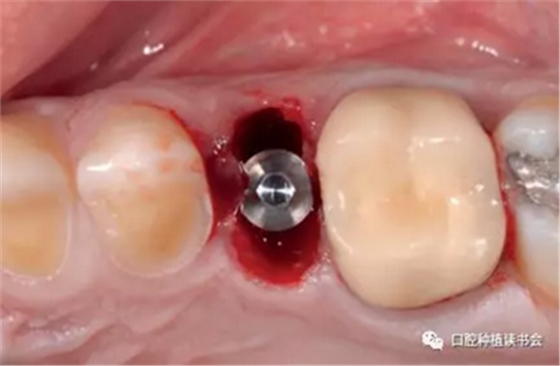

4.2.3 植入Nobel active種植系統(tǒng) RP 13mm種植體,植入扭矩大于45Ncm,初期穩(wěn)定性良好(圖11、圖12))。

圖11 使用Nobel active手用植入扳手精確控制植入方向

圖12 種植體初期穩(wěn)定性良好,注意與唇側骨板間的間隙